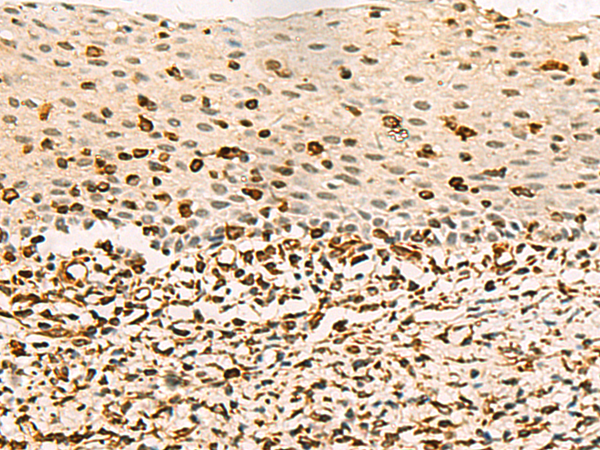

分类: 科研抗体货号: P09389别名:应用: WB,IHC反应种属: Human